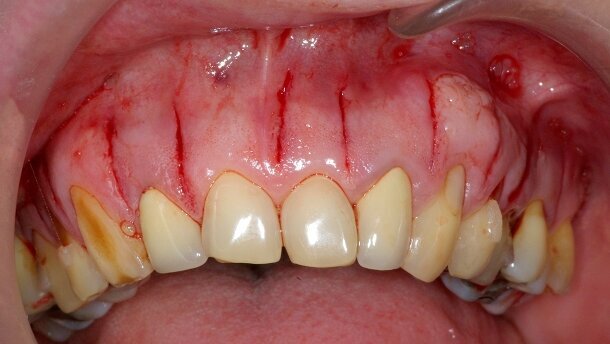

_Figs. 2a–d_Situation postchirurgicale immédiate maxillaire et mandibulaire.

_Figs. 6a–c_Situation postchirurgicale immédiate maxillaire. Nous avons réalisé l'intervention à la mandibule à 15 jours d'intervalle, selon le souhait de la patiente.